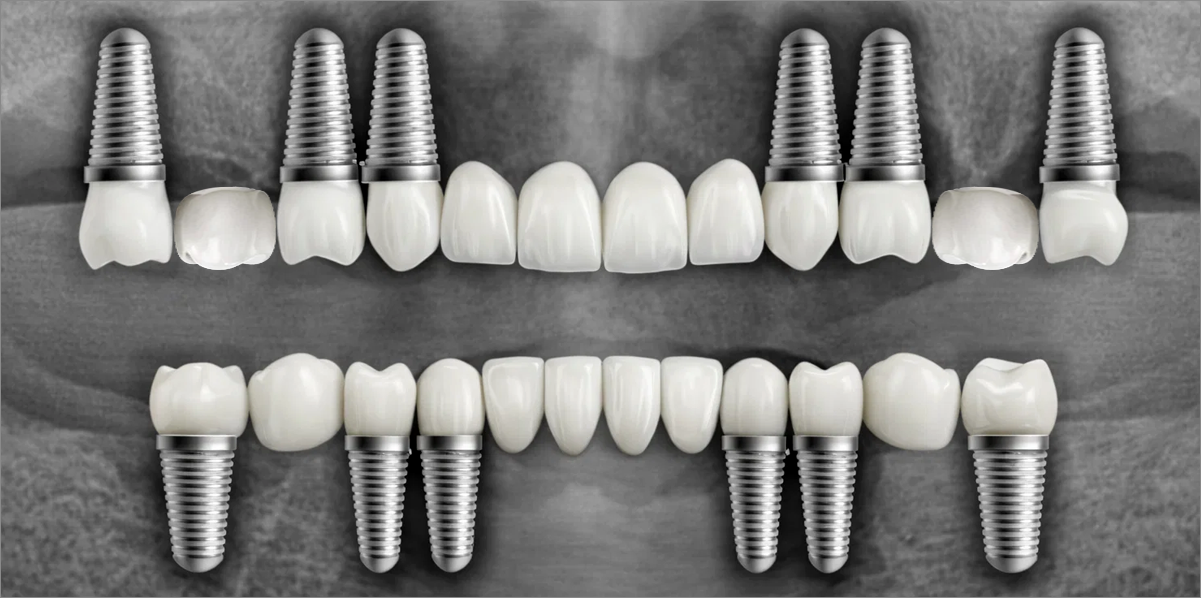

전체 임플란트

위 아래 치아가 정확하게 맞아야하는 고난이도 임플란트

임상 경험이 많은 숙련된 전문의의 섬세한 기술력이 중요합니다.